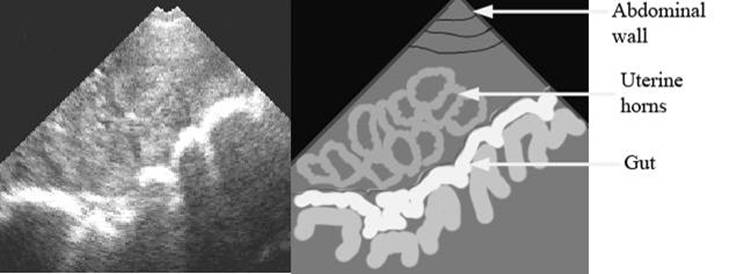

Not pregnant

repro draw preg not label.jpg